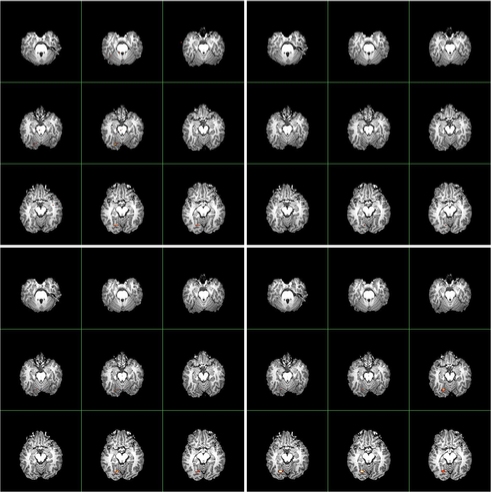

A comparison of the activated brain regions using the and procedures is visualized in Figure 9. The level is used to carry out the multiple comparisons. The conventional procedure finds more tiny scattered active voxels, which are more likely to be falsely discovered. In contrast, the procedure finds activation in much more clustered regions of the brain.